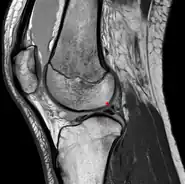

Posterior meniscofemoral ligament on MRI, sagittal

Posterior meniscofemoral ligament (Wrisberg) behind the posterior horn of the lateral meniscus close to its insertion. Sometimes wrongly interpreted as a meniscal tear.